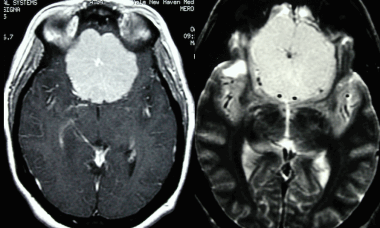

(Слева) Бесконтрастная КТ, аксиальный срез: определяется дольчатое гиперденсное объемное образование, расположенное по ходу намета мозжечка справа.

(Справа) МРТ, FLAIR, аксиальный срез: у этого же пациента визуализируется гипоинтенсивное многодольчатое объемное образование с перифокальным отеком и масс-эффектом на IV желудочек.